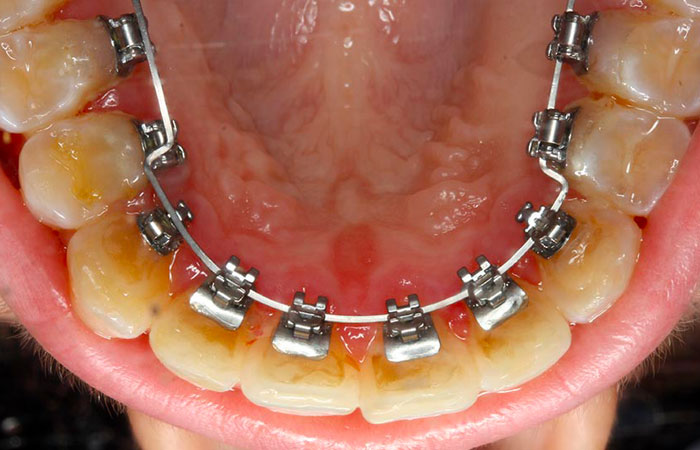

Bagues linguales outlet

Bagues linguales outlet, L orthodontie invisible pour les adolescents enfin une realite outlet

Orthodontiste Val de Marne 94 Interview d un patient avec beance outlet, Ma chirurgie Maxillo faciale Vlog 7 Appareil dentaire lingual temoignage outlet, Appareil Dentaire Adulte bagues lingual invisible Orthodontie Adulte outlet, Orthodontiste Paris Orthodontie linguale Paris outlet, L orthodontie invisible pour les adolescents enfin une realite outlet, Gouttieres invisibles ou bagues quelle solution choisir outlet, Bagues linguales hotsell ou invisalign outlet, L orthodontie invisible pour les adolescents enfin une realite outlet, orthodontie linguale Win specialite du cabinet du Dr Chassaing outlet, Lingual Braces The Dental Chambers Kensington outlet, Orthodontie adulte Dentiste Tremblay en France 93 outlet, Orthodontie Linguale a Paris Dr Issembert Orthodontiste outlet, Gouttieres invisibles ou bagues quelle solution choisir outlet, L orthodontie invisible pour les adolescents enfin une realite outlet, Appareil dentaire lingual pour les adulte Appareil Dentaire outlet, Orthodontie adulte outlet, Orthodontiste Val de Marne 94 Etapes de l Orthodontie Linguale outlet, Bagues linguales Orthodontie Lancy outlet, Bagues linguales ORTHODONTIE GARLABAN outlet, Orthodontie linguale finies les bagues apparentes outlet, Lingual Dr Soubrie Orthodontiste Voisins le Bretonneux Orthodontie 78 outlet, FAQ Quels sont les avantages et les inconvenients de l orthodontie linguale outlet, L orthodontie linguale SFODF outlet, Centre medico dentaire Blaise Pascal Dentiste a Trappes outlet, L essentiel sur les attaches linguales Centre dentaire des Tilleuls outlet, Orthodontie linguale Orthodontiste a Bordeaux Dr Francois Darque chirurgien dentiste outlet, Orthodontie Linguale toutes les infos a savoir Orthodontie Adulte outlet, Le traitement orthodontique lingual un appareil orthodontique totalement invisible outlet, Bagues et orthodontie le guide sur les differentes techniques outlet, Orthodontie Linguale Paris appareil dentaire lingual outlet, Orthodontie Linguale a Paris Dr Issembert Orthodontiste outlet, Les bagues et l orthodontie 3 grandes categories d appareils dentaires outlet, Lingual Orthodontics by Dr. Issembert Orthodontist outlet, Appareil dentaire invisible lingual Dr Ohana Chpindel outlet, Bagues linguales Orthodontie Lancy outlet, Product Info: Bagues linguales outlet.